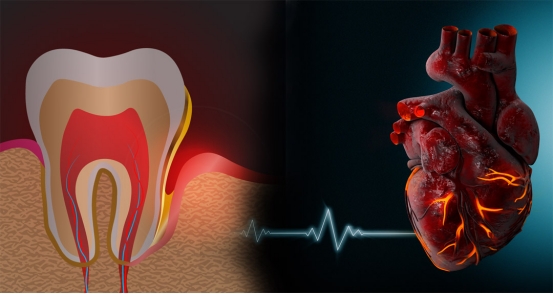

对于有冠心病的患者,如果心功能尚好,近6个月没有心肌梗死、心绞痛的患者,在医生充分检查和评估后,多数可以拔牙。

冠心病与拔牙